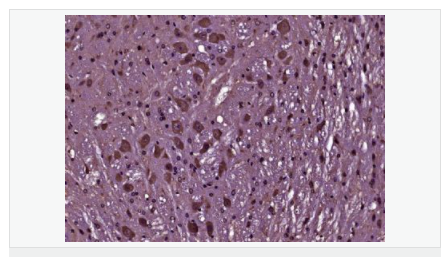

| 產(chǎn)品應用 | WB=1:500-2000 ELISA=1:5000-10000 IHC-P=1:100-500 IHC-F=1:100-500 Flow-Cyt=1μg/Test IF=1:100-500 (石蠟切片需做抗原修復) not yet tested in other applications. optimal dilutions/concentrations should be determined by the end user. |